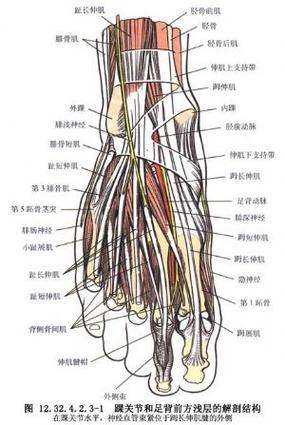

踝关节不稳定4踝伸肌下支持带解剖

踝关节解剖分析

值得收藏踝关节解剖分析高清图文详解